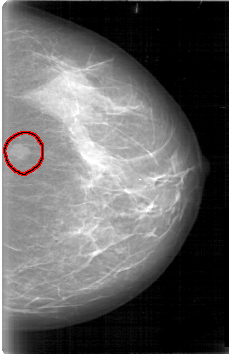

D_4006_1.LEFT_MLO

LEFT_MLO LINES 5281 PIXELS_PER_LINE 3571 BITS_PER_PIXEL 12 RESOLUTION 43.5 OVERLAY

FILE: D_4006_1.LEFT_MLO.OVERLAY

TOTAL_ABNORMALITIES 1

ABNORMALITY 1

LESION_TYPE MASS SHAPE OVAL MARGINS OBSCURED

ASSESSMENT 0

SUBTLETY 5

PATHOLOGY BENIGN

TOTAL_OUTLINES 1

BOUNDARY